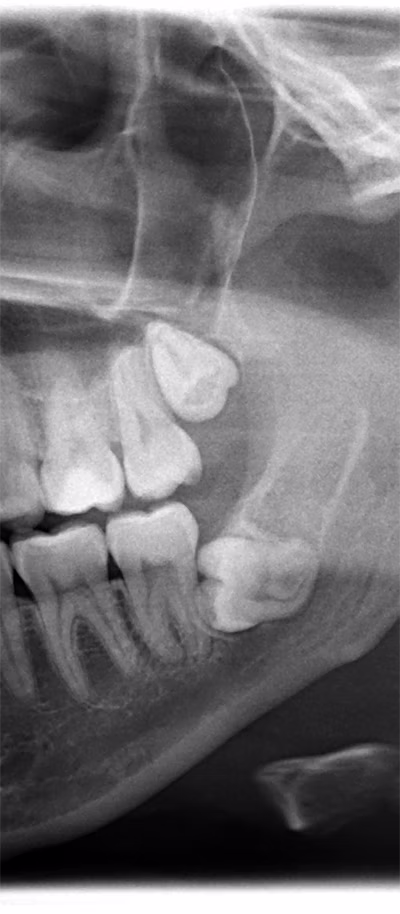

Impacted teeth occur when a tooth fails to fully emerge through the gums. This is common with wisdom teeth, some permanent teeth, and stubborn baby teeth. Causes can include overcrowding, abnormal growth patterns, or excess teeth in the jaw. Impacted teeth may lead to pain, difficulty chewing, or misalignment. In some cases, symptoms are not visible until detected on an X-ray. At our Leander office, we provide customized solutions for impacted teeth, including orthodontic guidance to help teeth erupt correctly. For problematic wisdom teeth, expert extraction is often the recommended solution.

Third molars, or wisdom teeth, typically appear in late adolescence or early adulthood. They often cause complications due to insufficient space for proper eruption, leading to:

- Pain and swelling

- Decay and gum infection

- Misalignment of surrounding teeth

- Cysts or tissue damage

Almost 90% of adults experience at least one impacted wisdom tooth. Our Leander dentists are trained to remove wisdom teeth safely and comfortably, protecting surrounding teeth, nerves, and tissues.